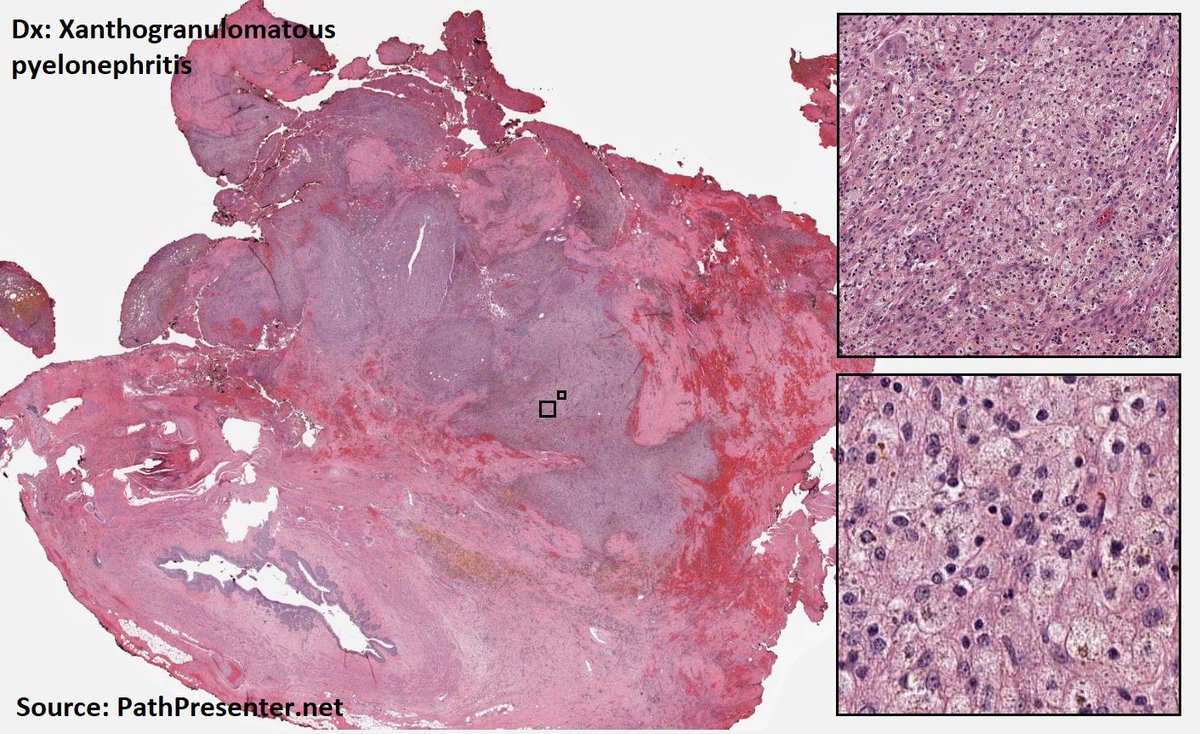

Histology flash card Xanthogranulomatous pyelonephritis Uncommon/rare Destructive inflam process that may resemble RCC Oft assoc with chronic pyelonephritis due to E. coli or Proteus Histo Extensive foamy histiocytes #MedTwitter #PathTwitter